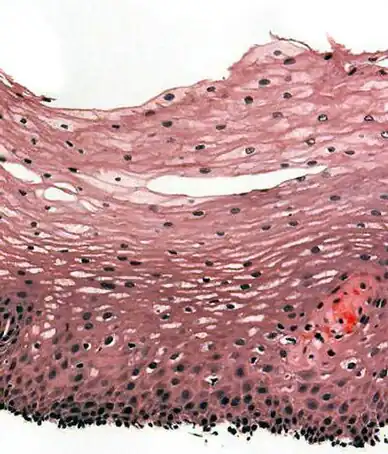

The human esophagus has a mucous membrane consisting of a tough stratified squamous epithelium without keratin, a smooth lamina propria, and a muscularis mucosae.[7] The epithelium of the esophagus has a relatively rapid turnover and serves a protective function against the abrasive effects of food. In many animals, the epithelium contains a layer of keratin, representing a coarser diet.[20]

The muscular layer of the esophagus has two types of muscle. The upper third of the esophagus contains striated muscle, the lower third contains smooth muscle, and the middle third contains a mixture of both.[7] Muscle is arranged in two layers: one in which the muscle fibers run longitudinal to the esophagus, and the other in which the fibers encircle the esophagus. These are separated by the myenteric plexus, a tangled network of nerve fibers involved in the secretion of mucus and in peristalsis of the smooth muscle of the esophagus. The outermost layer of the esophagus is the adventitia in most of its length, with the abdominal part being covered in serosa. This makes it distinct from many other structures in the gastrointestinal tract that only have a serosa.[7]